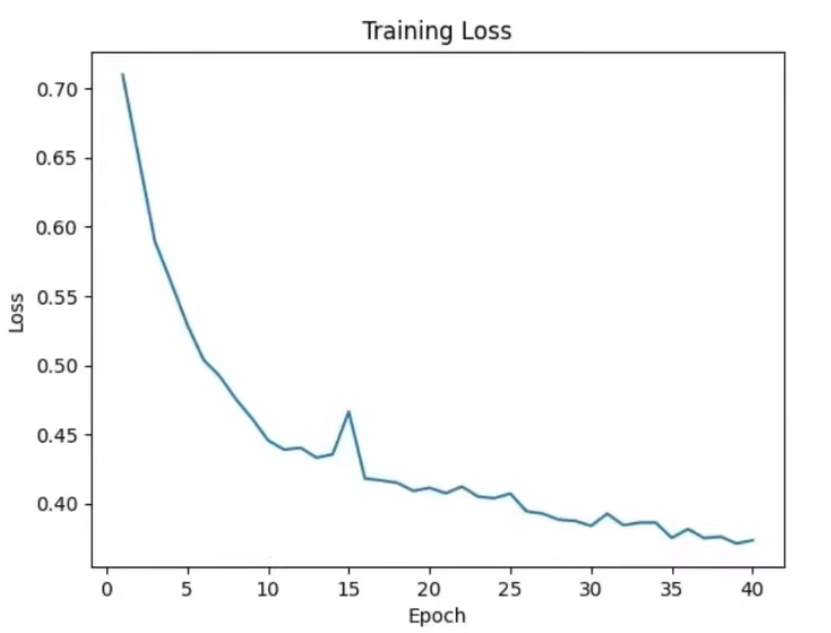

num_epochs = 100

for epoch in range(num_epochs):

print(f'Epoch [{epoch+1}/{num_epochs}], Loss: {loss.item()}')